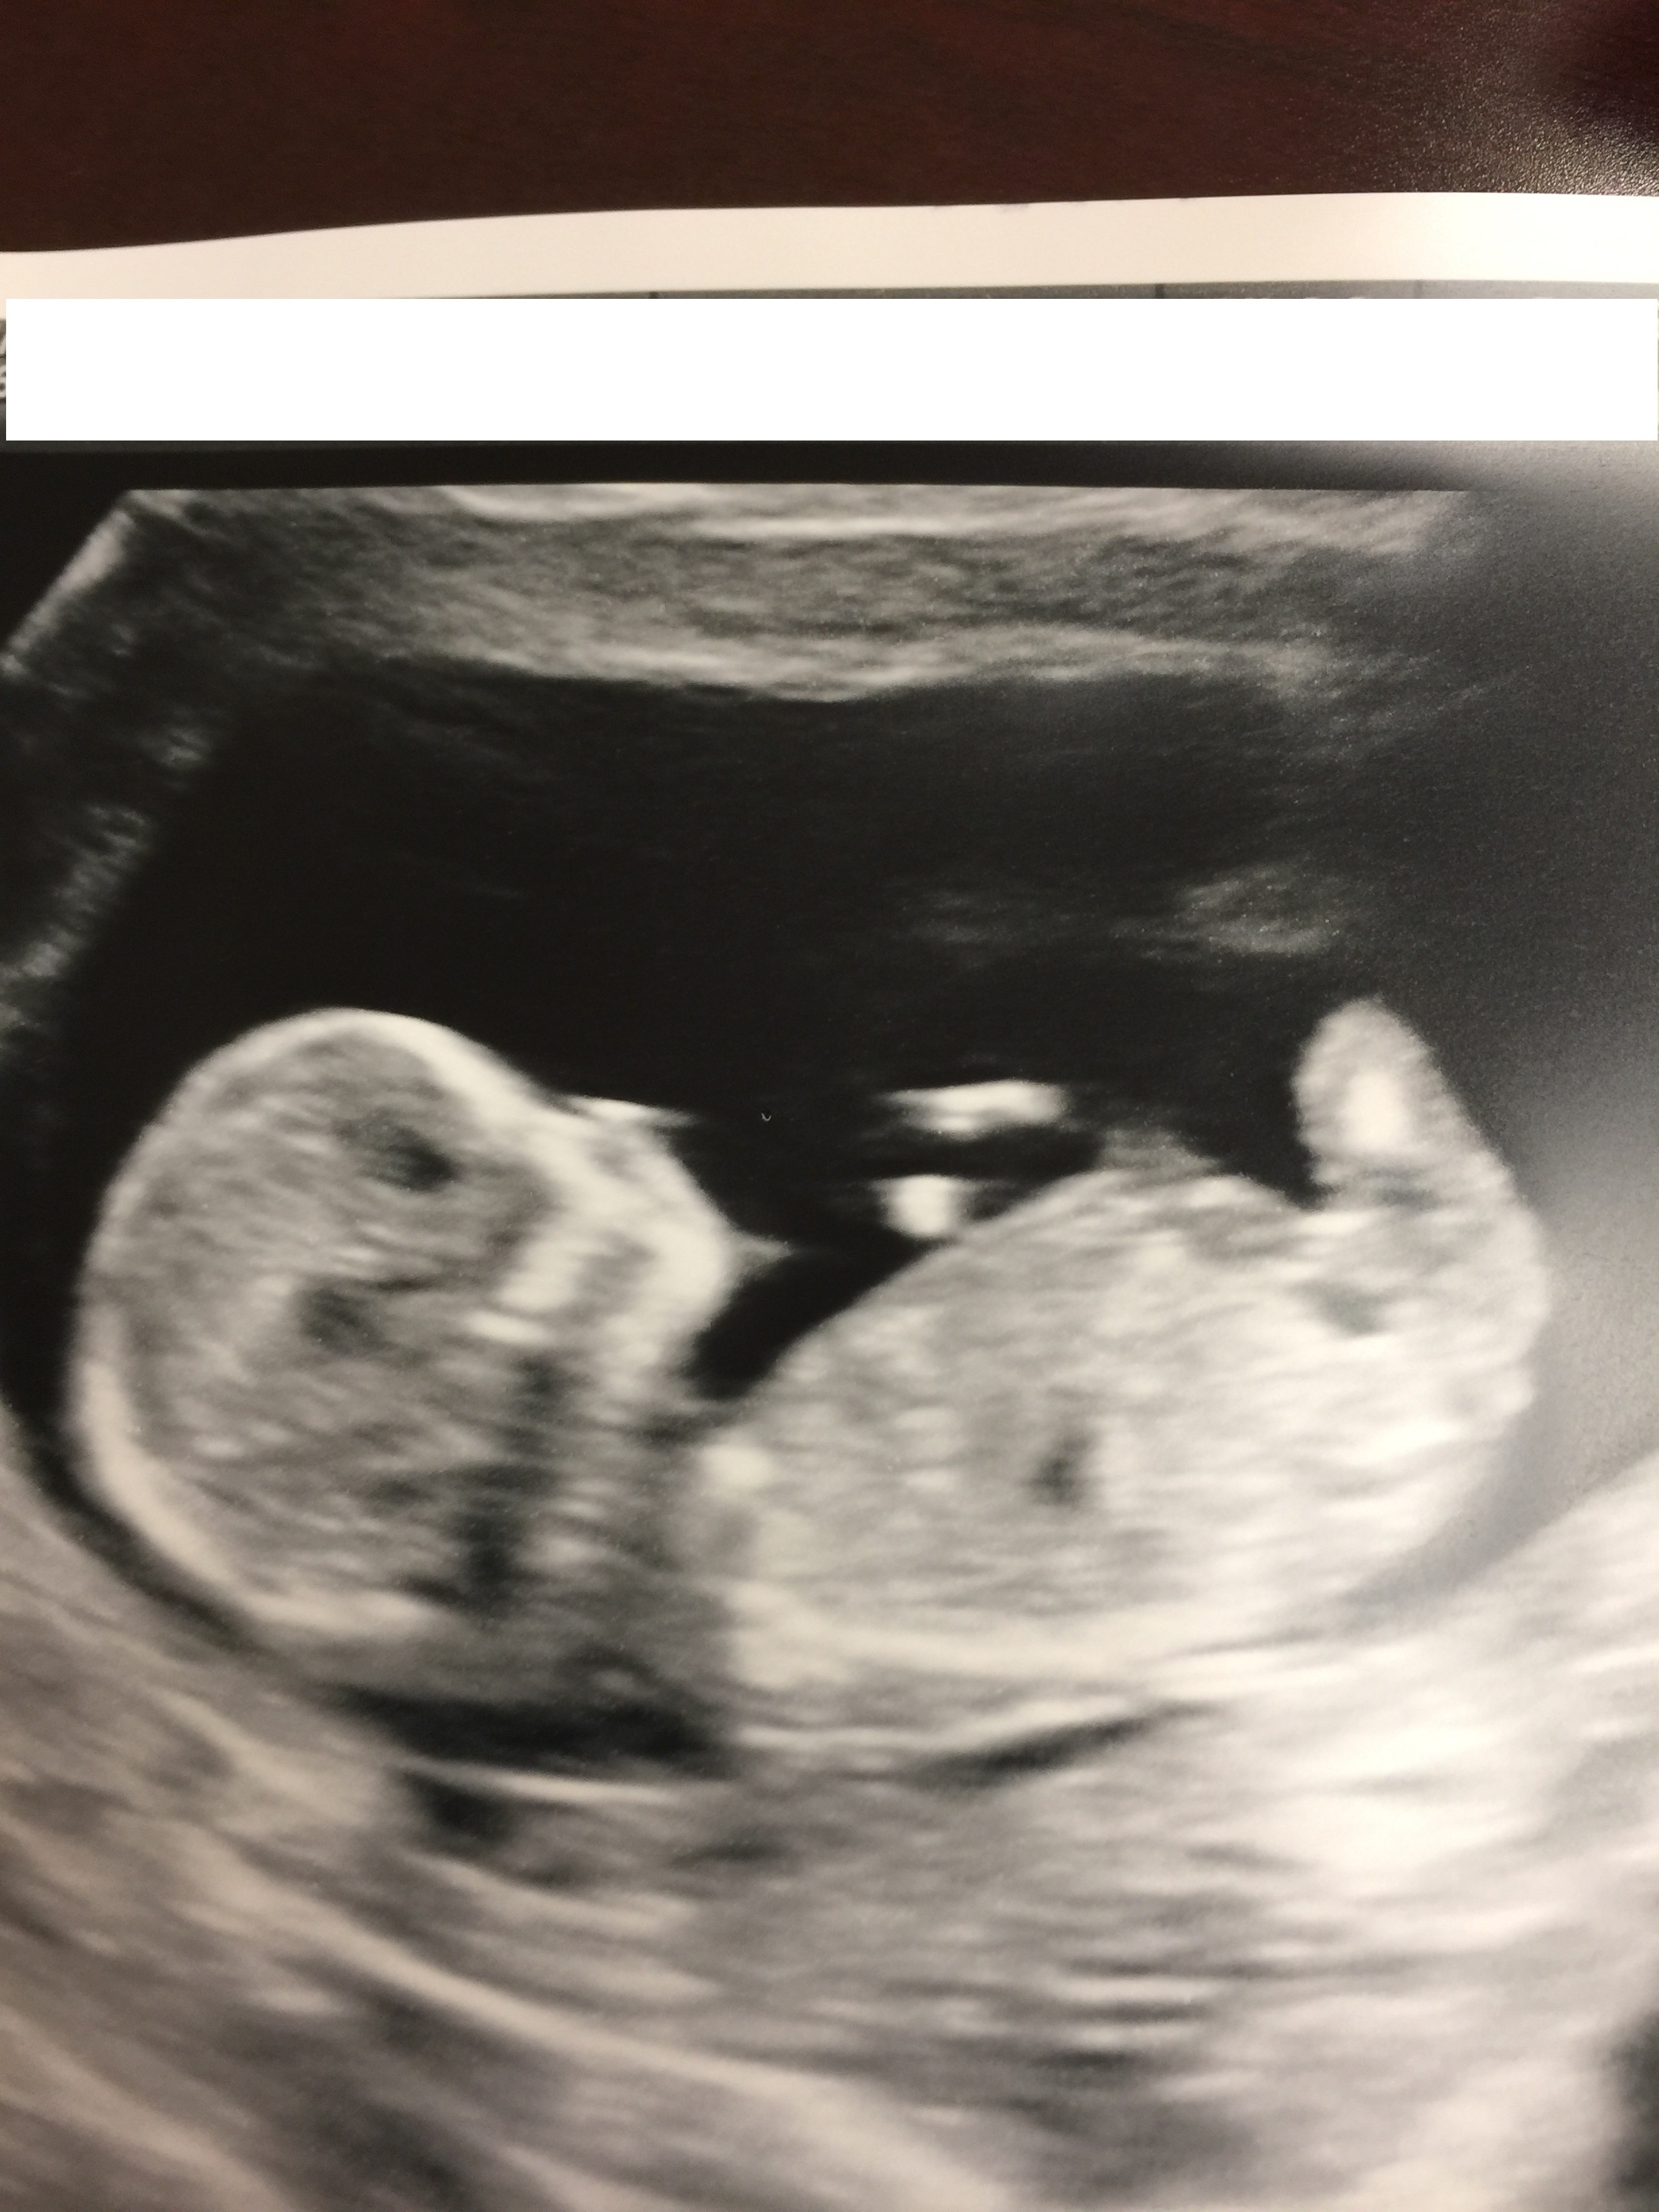

Maybe boy? Tentative boy lean from me, not sure though as nub looks flat but there could be stacking in pic 1? I'm still learning so look forward to seeing what the seasoned guessers say :)

Leaning boy from possible stacking in pic 1 too :)

Not sure, but maybe boy. Could also be a cord though. More pics or a video?